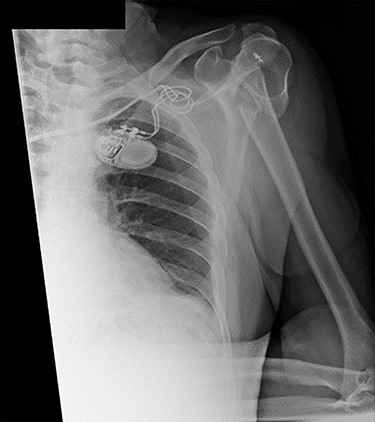

Examination and imaging of the patient revealed that during the fall, he had sustained a left surgical neck of humerus fracture (Fig. 1). Significant skin puckering was noted on the anterior aspect of the left shoulder over the fracture site, otherwise the arm was neurovascularly intact (Fig. 2). He was immediately reviewed by the orthopaedic team who offered surgical fixation of the fracture on the following morning, which was dependent on an appropriate anaesthetic assessment. The patient was in agreement and consented to proceed.

Antero-posterior view X-ray taken on day of admission, showing a left surgical neck of humerus fracture with anterior displacement of the proximal humeral shaft.